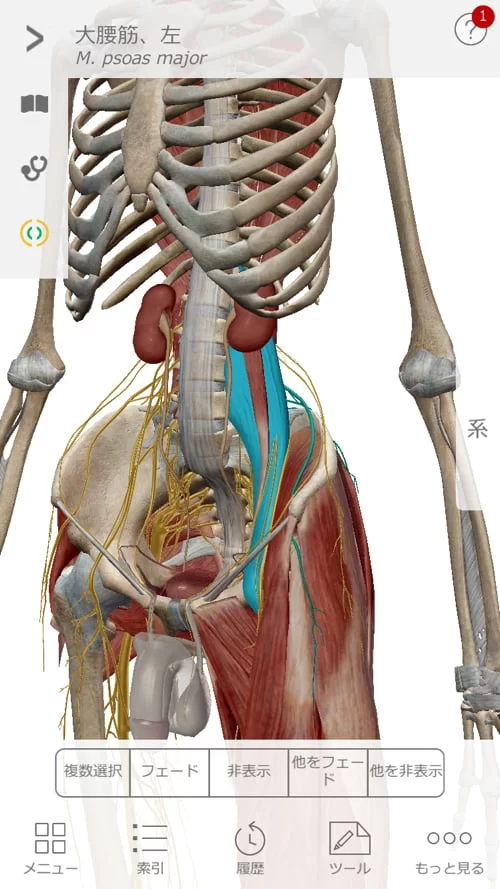

そして背骨と骨盤の前側を繋いでいる筋肉の硬直を解きます。

大腰筋や腸骨筋類。